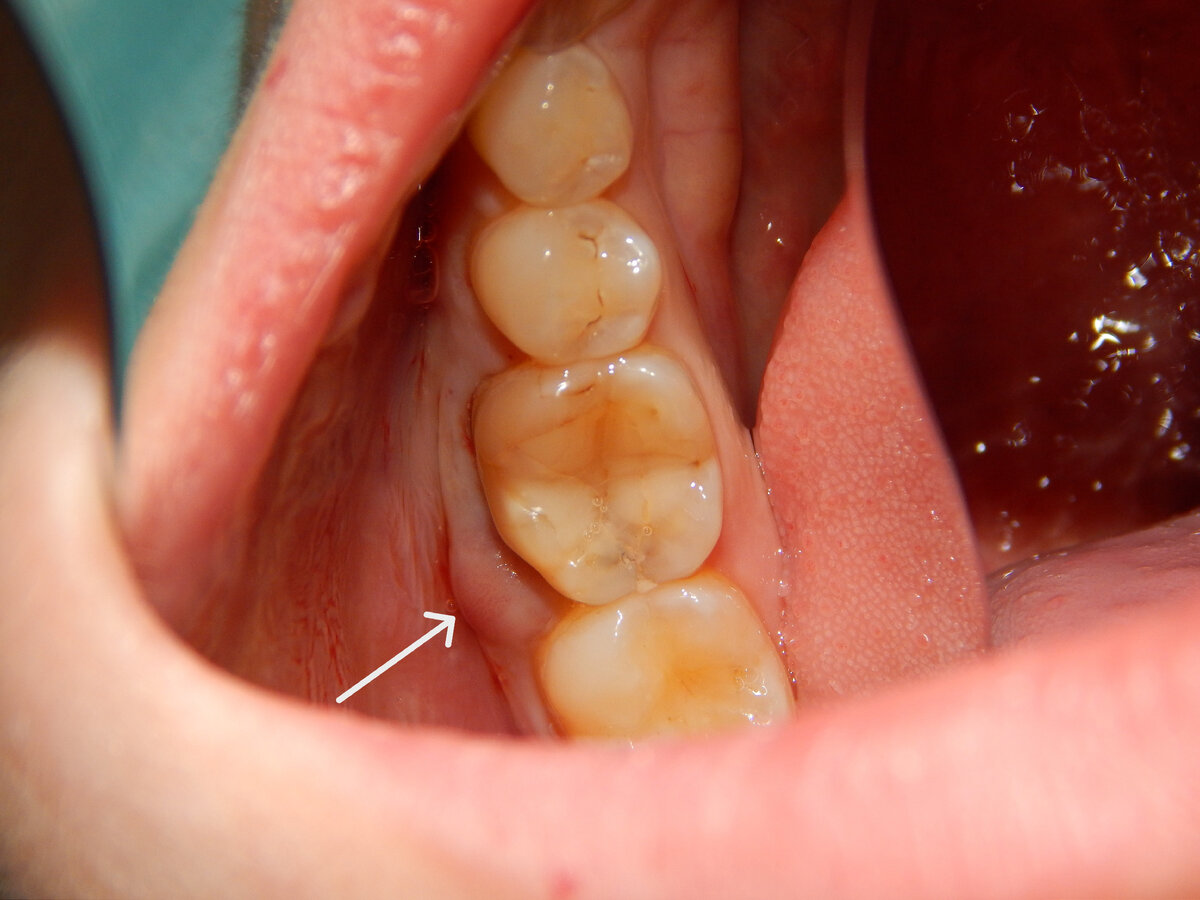

Пациент обратился с жалобами на появление шишечки на десне.

Исходная ситуация:

После изучения снимка и очистки зуба ультразвуком стало понятно, что под старой пломбой кариозный процесс, который напоминает червивое яблоко. Кажется, что свиду цел, а внутри червяк поел.

После снятия пломбы (вскрытие показало) я увидел трещину в дистальном корне:

А всему виной явился вторичный кариес из-за него ткани зуба внутри стали полыми(пустыми) и при нагрузке (при пережёвывании пищи) возникла трещина корня.

От трещины корня, началось микровоспаление в близлежащей костной ткани и это привело к образованию шишечки с щёчной стороны. Инфекция нашла выход по пути наименьшего сопротивления в щёку.